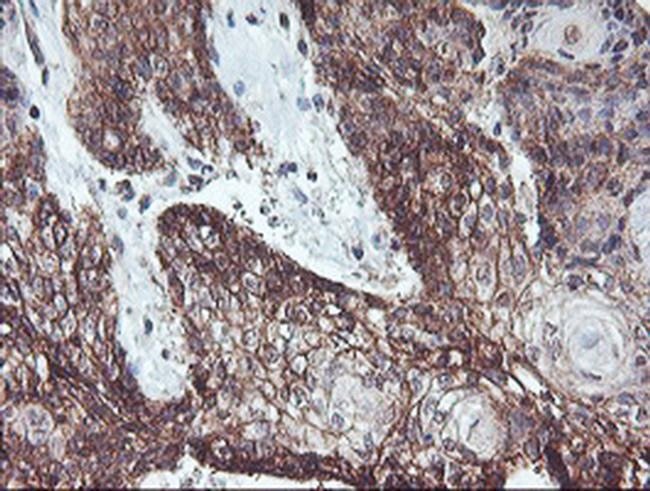

RFXANK Monoclonal Antibody for Western Blot, ICC/IF, IHC (P), Flow

| Applications | Flow Cytometry, Immunohistochemistry (Paraffin), Western Blot, Immunocytochemistry |